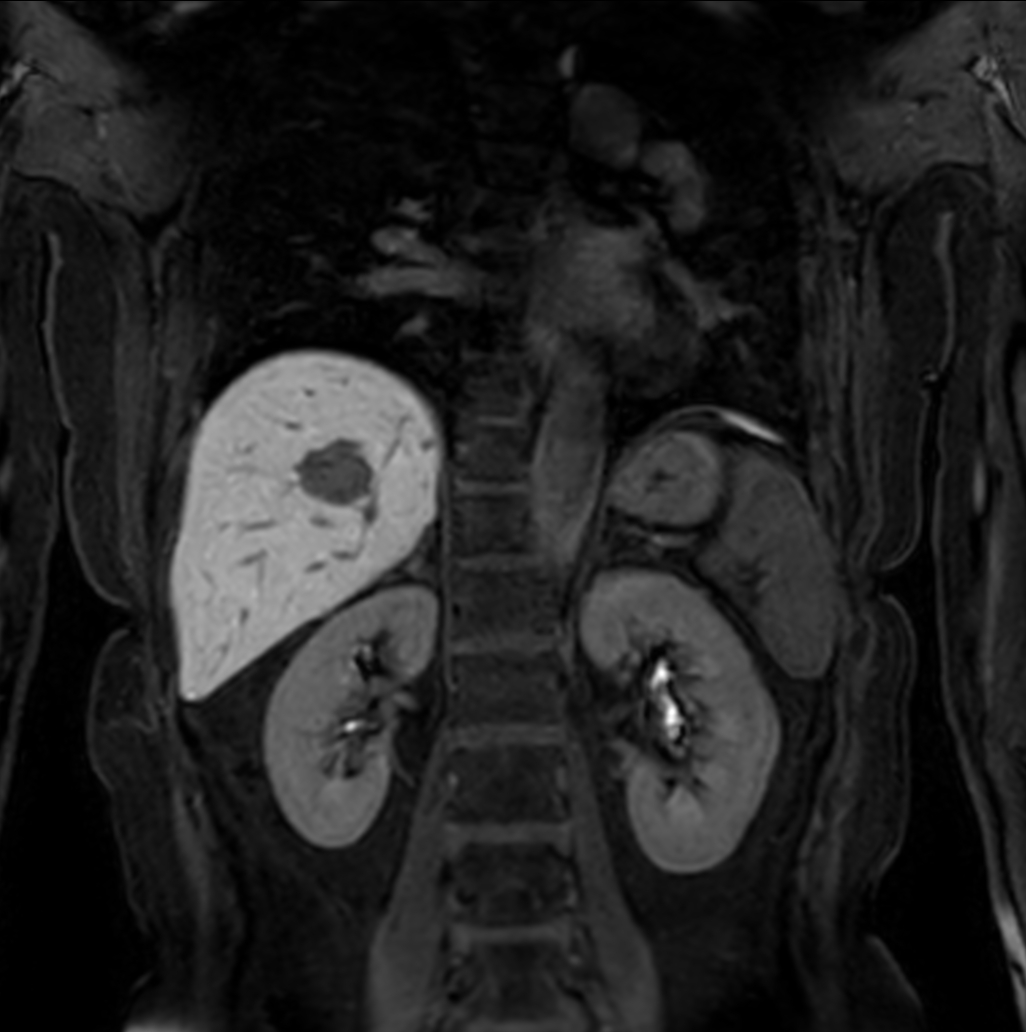

Coronal bTFE (MIP)